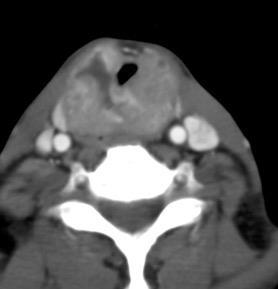

Carcinoma subglótico

Tumor poco frecuente. 1,8% de los tumores laríngeos.

Tendencia a invadir el anillo cricoideo y el esófago.

Ganglios + frecuentes

Mac Neill SD et al. Survival of patients with subglottic squamous cell carcinoma. Curr Oncol. 2018